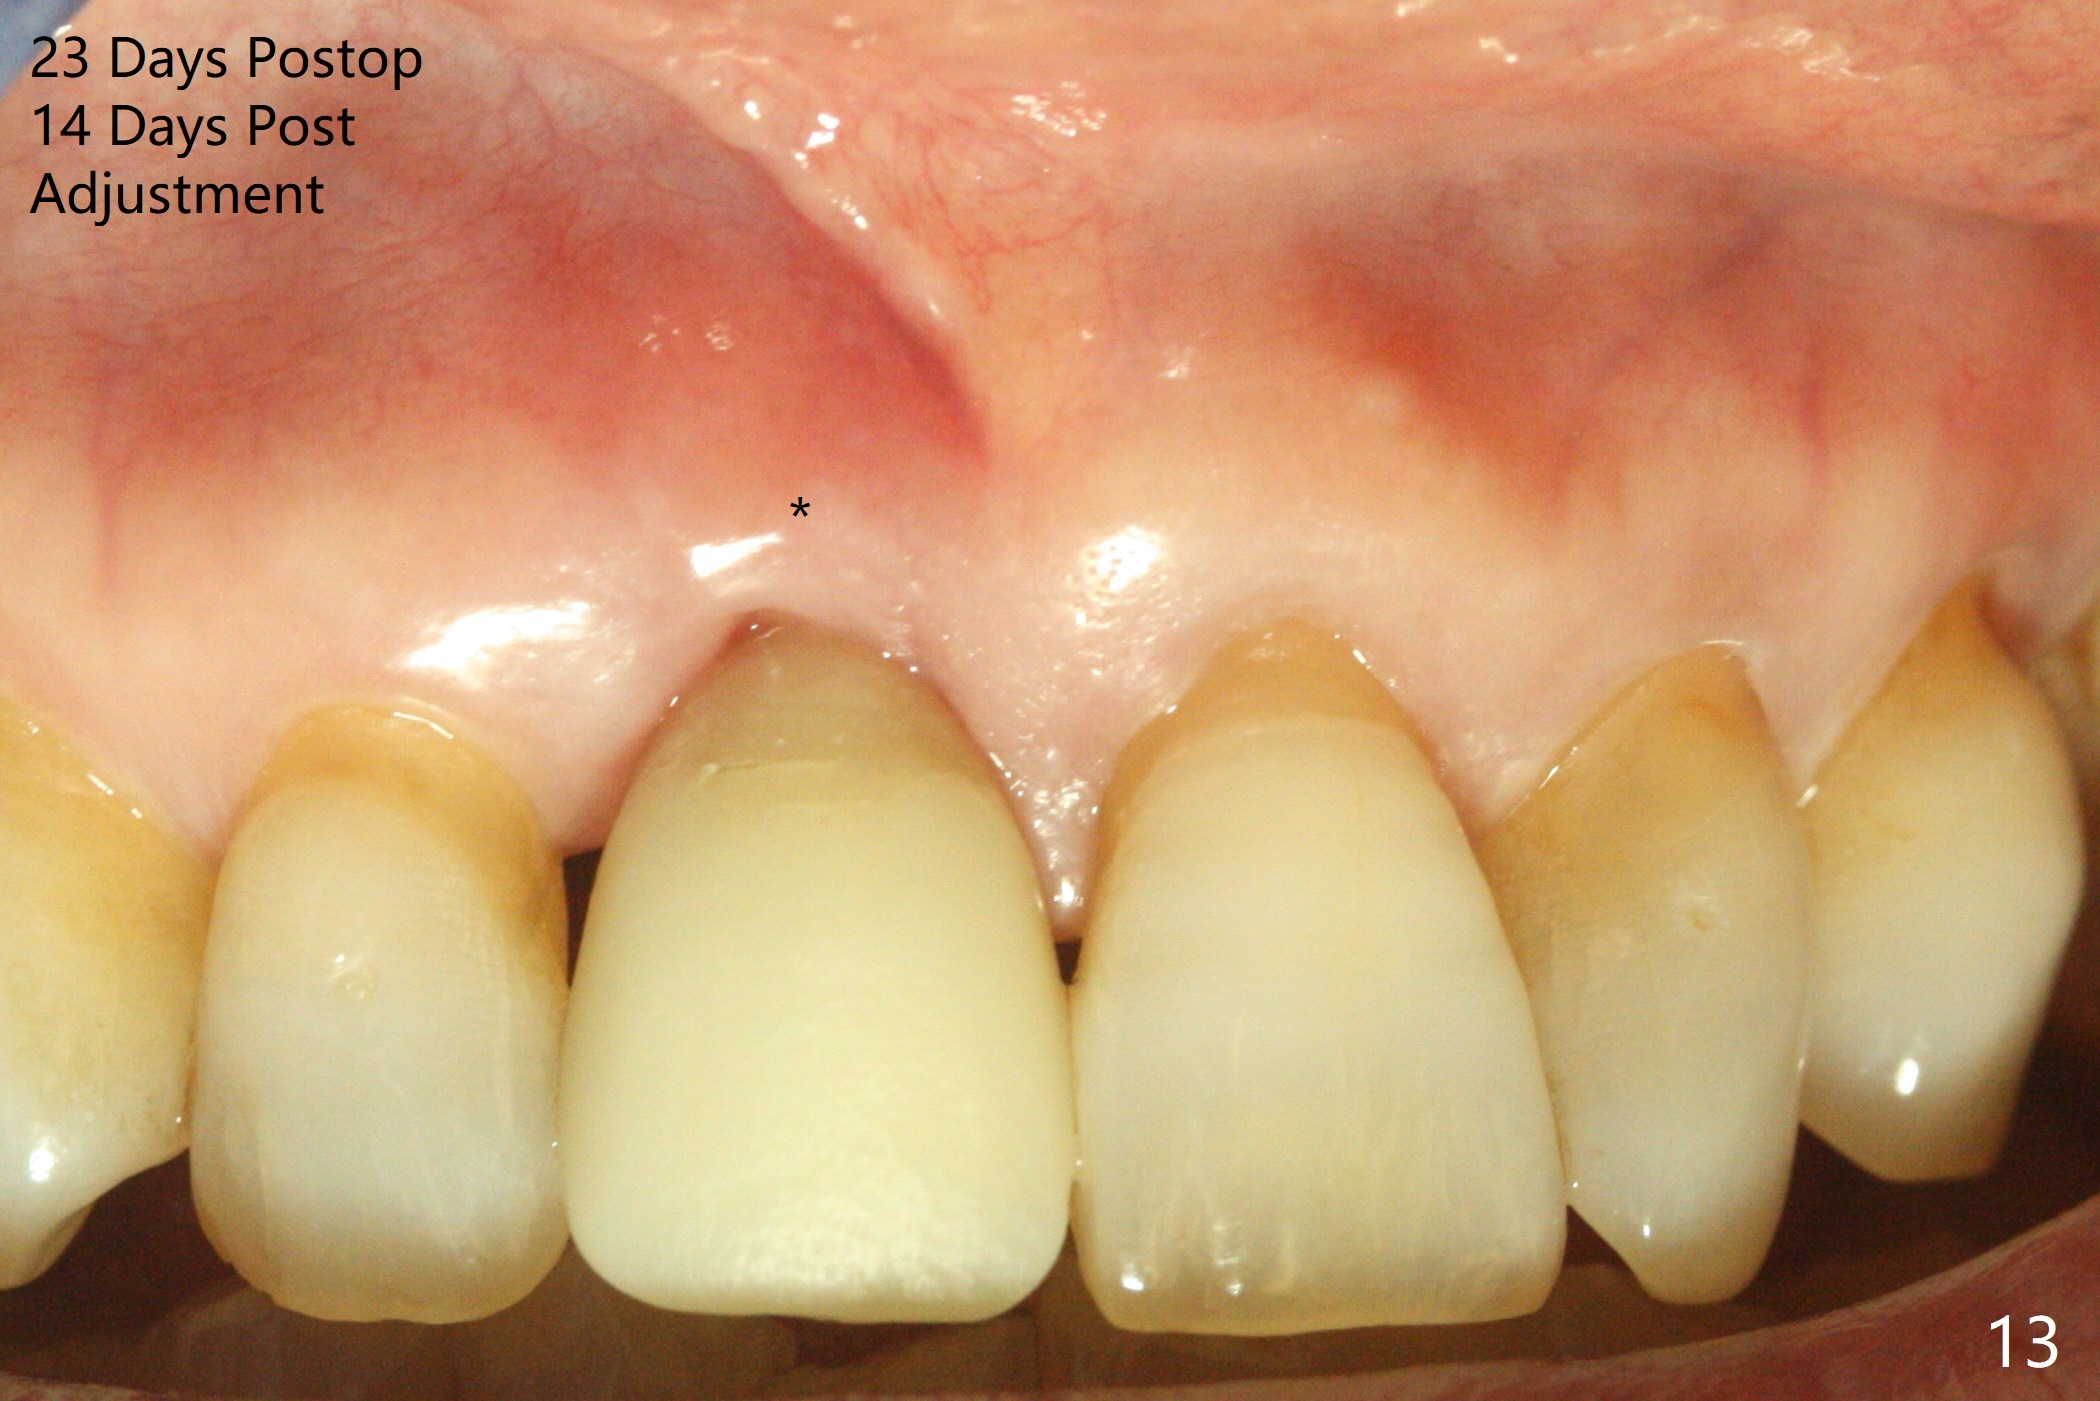

59岁女术前右下1,2切缘磨短后,右上1颊侧移位得到纠正(图一(咬合创伤))。拔牙后证实颊侧骨板缺失,钻洞始于腭侧(图二),当1.5毫米钻头感觉刚穿破鼻底时,置入2.5x14(4)毫米一段式植体,好像进入鼻腔,但是扭力<10Ncm(图三)。把一张PRF膜放入牙槽窝,一端紧贴颊侧牙龈腭侧,另一端放置颊侧牙龈颊侧(图四),然后开始用粘性骨粉(图五,七:*(100%皮质骨))充填颊侧间隙。后者填满时(图五:*),将外面一端PRF翻转覆盖牙槽窝开口,并插入基台固定(图六),最后插入龈下,用临时牙冠固定(图八(T),九(*:PRF))。术后九天牙龈退缩(图十:^),临时牙冠突出(*),后者龈缘和切缘进行调整,缩短(图十一,十二),少许骨粉暴露(图十二:>),十四天后牙龈往下生长,好像形成角化龈(图十三:*)。